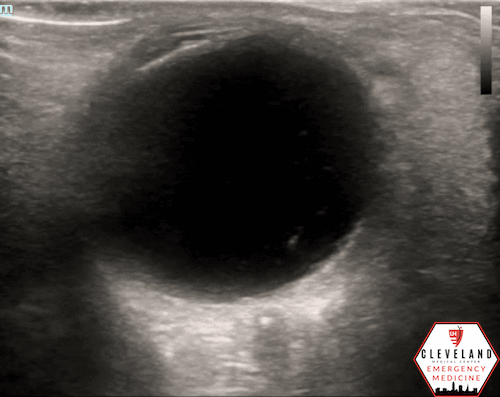

POCUS Findings: Ocular ultrasound revealed a small hyperechoic focus over the distal optic nerve in the retrobulbar space, raising concern for central retinal artery occlusion (CRAO) in the setting of painless monocular vision loss. Color doppler demonstrated diminished arterial flow in his region, further supporting the diagnosis.

A hyperechoic focus over the distal optic nerve — referred to as the retrobulbar spot sign — has been observed on ocular ultrasound in cases of CRAO and may help differentiate it from other causes of painless monocular vision loss (7,8). Illustrated in Figures 4-6, this finding is considered highly specific for embolic CRAO and, when present, is associated with a significantly lower likelihood of temporal arteritis (9). However, its true prevalence remains unclear, and most studies evaluating its diagnostic accuracy have been small. In one study, the retrobulbar spot sign demonstrated a sensitivity of 83% and specificity of 100% for CRAO (9).

If a hyperechoic spot is identified, consider using color Doppler to assess for diminished or absent arterial flow distal to the focus (see Figure 6). Keep in mind that Doppler signal is angle-dependent, and poor probe positioning may limit its reliability.

Figure 5. Retrobulbar hyperechoic spot sign from our patient’s case